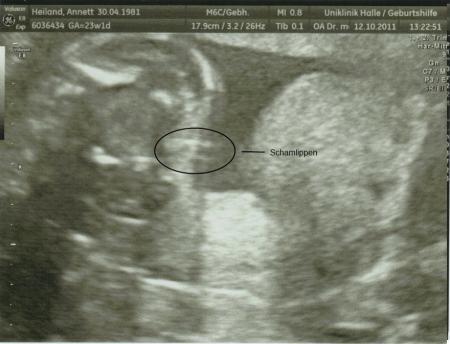

hallo ihr lieben. hatte ja heute mittag noch mal FD (zum 4. mal dieses SS ). also mit dem würmchen ist alles in ordnung. es sollten ja noch mal gesicht und wirbelsäule kontrolliert werden, da die das letzte mal nicht beurteilbar waren. aber dieses mal schon und es ist alles in ordnung. trotz das ich erst vor 3 wochen war und nur gesicht und wirbelsäule noch mal angekuckt werden sollten, hat er noch mal alles mit ausgemessen. hier mal die daten: BPD (kopf, scheiteldurchmesser) 54,4 mm FOD (kopf, vorne bis hinten) 72,3 mm KU (kopfumfang) 199,9 mm AU (bauchumfang) 170,0 mm FL (oberschenkel) 42,0 mm größe ist 29,4 cm mit einem gewicht von 525 gramm. dann wurde, weil wir es wollten, noch mal nach dem geschlecht gekuckt und es ist nichts mehr angewachsen, also bleibts (gott sei dank, wegen der wände die ich schon in rosa gemalt hab) beim mädchen. weil wir ja beim letzten mal leider kein bild vom gesicht machen konnten, hab ich dem arzt gesagt, wenn wir kein schönes bild kriegen, würde ich gerne eins vom geschlecht haben. da sagt der doch glatt "ahhhh, ein porno bild wollen sie haben" na ja, schlussendlich haben wir jetzt eins vom gesicht und eins vom geschlecht. als wir dann fertig waren sagte er noch zu uns, da die kleine schon so lange beine hat, können wir sie gleich bei germanys next topmodel anmelden, da passt sie dann gut rein, weil sie ja so groß ist alles in allem war es ein toller termin, sehr lustig mit dem arzt und ich bin froh, das alles ok ist und das es immer noch ein mädchen ist. das erste bild ist vom gesicht. auf den ersten blick siehts aus wie ein alien, man muss etwas länger hin schauen, da sieht man versteckt die kleine stubsnase, die nasenlöcher, die lippen usw. schaut einfach etwas länger hin. achso, die kleine sieht wie ihr papa aus, auf dem bildschirm haben wir es richtig gesehen. so das wars von mir. war ja nun lang genug. morgen noch mal FA besuch, vielleicht kriegen wir das gesicht morgen noch schöner hin. lg annett

habs für euch markiert, denn wenn man es nicht weiß wos liegt, kann man es glatt übersehen. lg annett